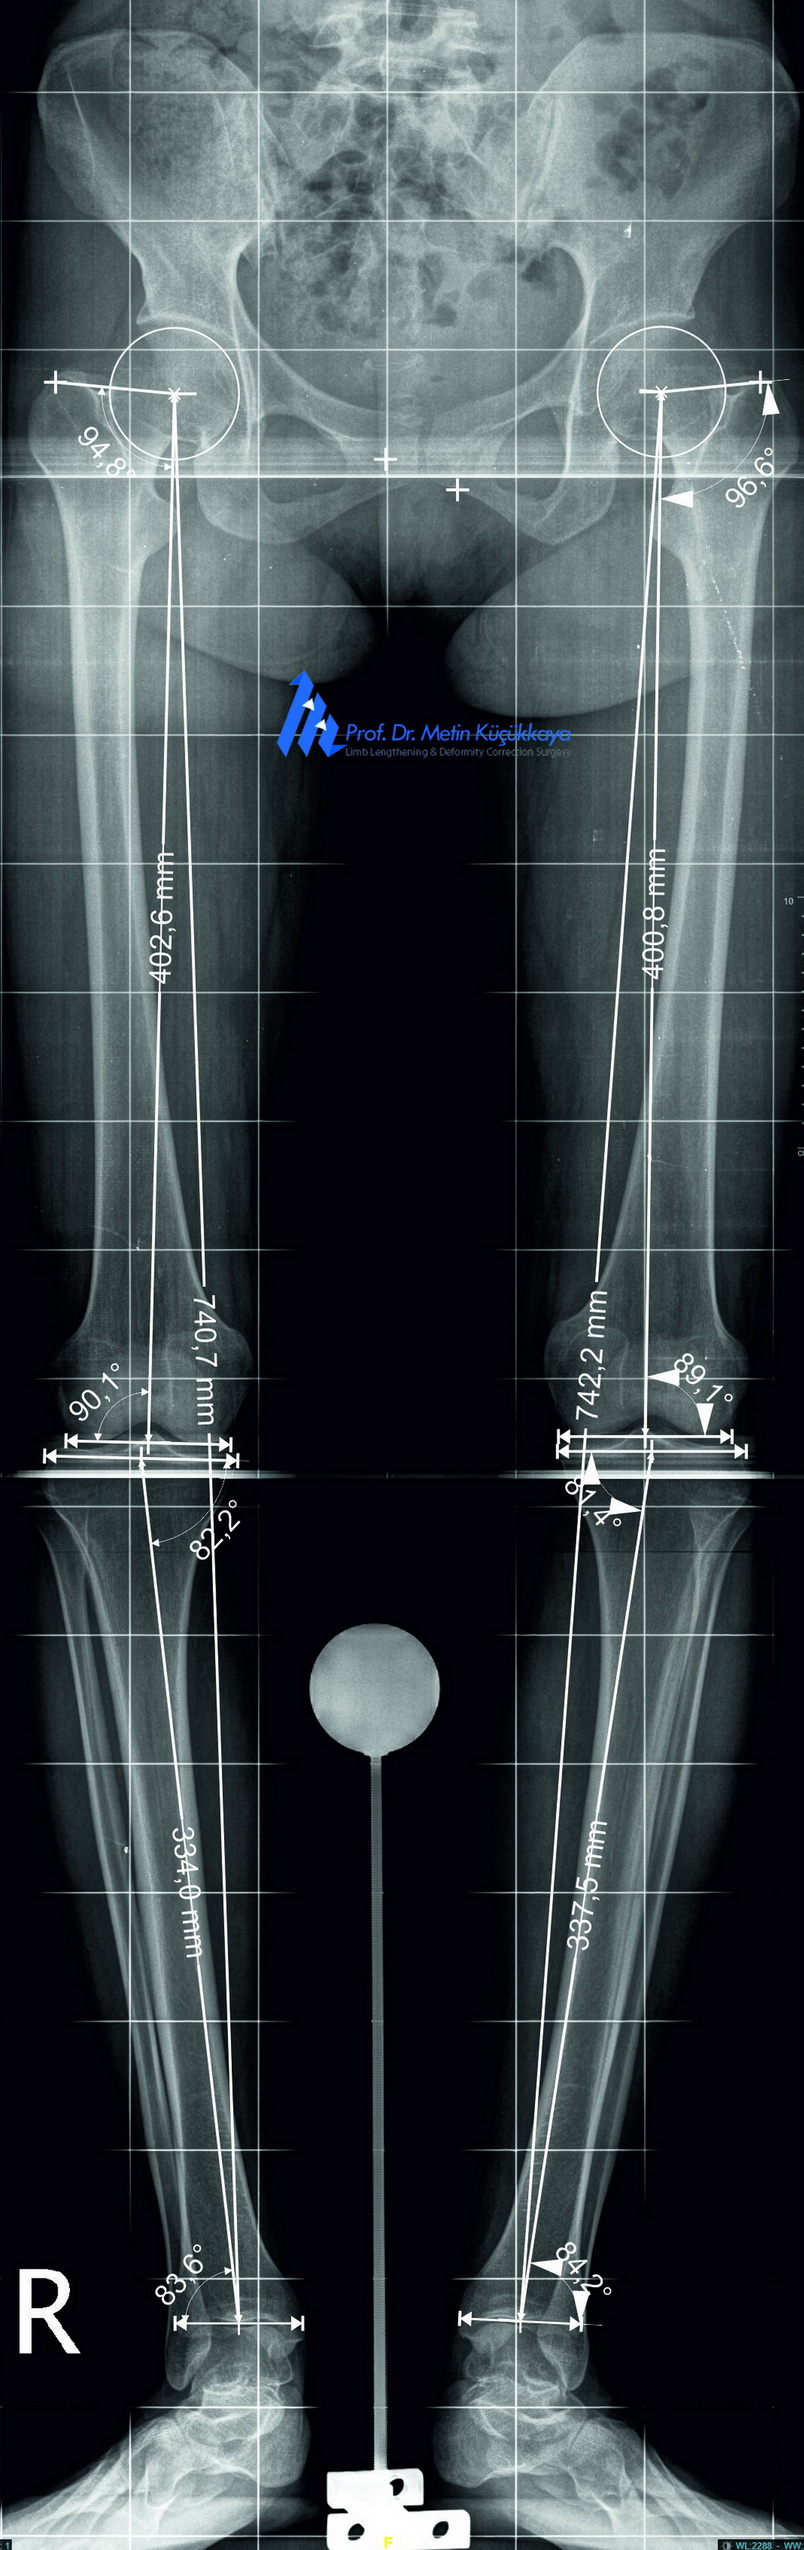

Preoperative clinical photograph and calibrated long-standing radiographs with CorelDRAW®-based measurements showing mild bilateral tibial bowing and mechanical axis deviation.

📐 Preoperative Planning:

The surgical plan was created using:

- Calibrated long-standing radiographs

- The End Point First (EPF) Method for accurate mechanical axis restoration

- CorelDRAW®–based digital preoperative planning

- Careful analysis of wedge opening, correction angle, axis deviation, and avoidance of over- or under-correction